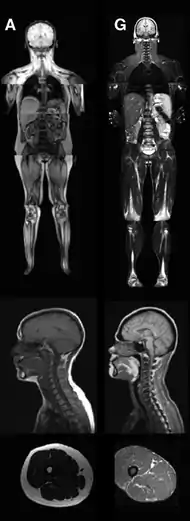

MRI of control patient vs. diseased patient.

An MRI image illustrating the lack of subcutaneous fat of a patient with the disease (G) compared to a control patient (A)